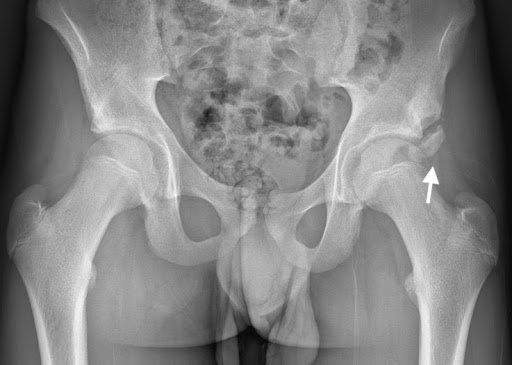

The mechanism of injury involved a forceful football kick, placing rectus femoris under high load, leading to avulsion of AIIS (figures 10 and 11).

Figure 10 – AP pelvic x-ray

Figure 11- Ultrasound AIIS

Progressive heterotopic calcification of the displaced apophysis and scar (subsequently demonstrated on CT scan), led to subspinous hip impingement and marked loss of sporting function and range of movement.